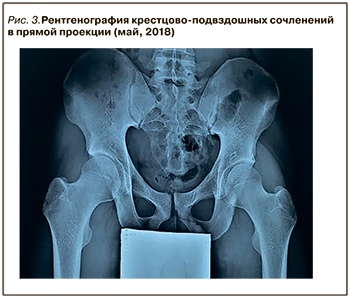

В феврале 2018 г. на фоне стрессовой ситуации пациент обратился с обострением псориаза волосистой части головы (с выраженным шелушением и покраснением), суставного синдрома (припухлость и боль в голеностопных суставах – 60 мм по визуально-аналоговой шкале), а также с впервые появившейся выраженной болью во всех отделах позвоночника (70 мм по визуально-аналоговой шкале), чаще возникавшей ночью и в периоды покоя и облегчавшуюся после движения, с длительной утренней скованностью. Данные лабораторных исследований: резкое повышение СРБ (32 мг/л), ASDASCRP=3,6. Ввиду появления характерной симптоматики и высокого риска прогрессирования назначено дообследование (МРТ и рентгенография крестцово-подвздошных сочленений). По результатам МРТ крестцово-подвздошных сочленений в режимах T1, STIR обнаружены признаки острого (двусторонний остеит крестцово-подвздошных сочленений) и хронического («бэкфил», эрозии) воспаления (рис.2), по данным рентгенографии крестцово-подвздошных сочленений – признаки двустороннего сакроилеита 2 стадии (рис. 3).

В феврале 2018 г. на фоне стрессовой ситуации пациент обратился с обострением псориаза волосистой части головы (с выраженным шелушением и покраснением), суставного синдрома (припухлость и боль в голеностопных суставах – 60 мм по визуально-аналоговой шкале), а также с впервые появившейся выраженной болью во всех отделах позвоночника (70 мм по визуально-аналоговой шкале), чаще возникавшей ночью и в периоды покоя и облегчавшуюся после движения, с длительной утренней скованностью. Данные лабораторных исследований: резкое повышение СРБ (32 мг/л), ASDASCRP=3,6. Ввиду появления характерной симптоматики и высокого риска прогрессирования назначено дообследование (МРТ и рентгенография крестцово-подвздошных сочленений). По результатам МРТ крестцово-подвздошных сочленений в режимах T1, STIR обнаружены признаки острого (двусторонний остеит крестцово-подвздошных сочленений) и хронического («бэкфил», эрозии) воспаления (рис.2), по данным рентгенографии крестцово-подвздошных сочленений – признаки двустороннего сакроилеита 2 стадии (рис. 3).

Вследствие присоединения новых клинических симптомов в виде воспалительной боли в спине, патогномоничных признаков на рентгенографии и МРТ крестцово-подвздошных сочленений проведена ревизия прежнего диагноза и выставлен новый: «АС, очень высокой активности, HLA-B27+, Ro-стадия сакроилеита 2, МРТ-остеит, артрит, энтезит, дактилит в анамнезе, псориаз волосистой части головы».

Особенностью данного клинического случая является дебют заболевания с периферического артрита, наличие у пациента псориаза, энтезита, дактилита в анамнезе, в результате чего был диагностирован ПсА и назначен метотрексат как препарат выбора в терапии артрита и псориаза. В связи с изменением клинической картины (появление воспалительной боли в спине), а также с учетом ранее выявленного HLA-B27 и появления изменений по результатам МРТ и рентгенографии крестцово-подвздошных сочленений (признаки острого и хронического воспаления) в короткие сроки диагноз ПсА был пересмотрен и выставлен АС.